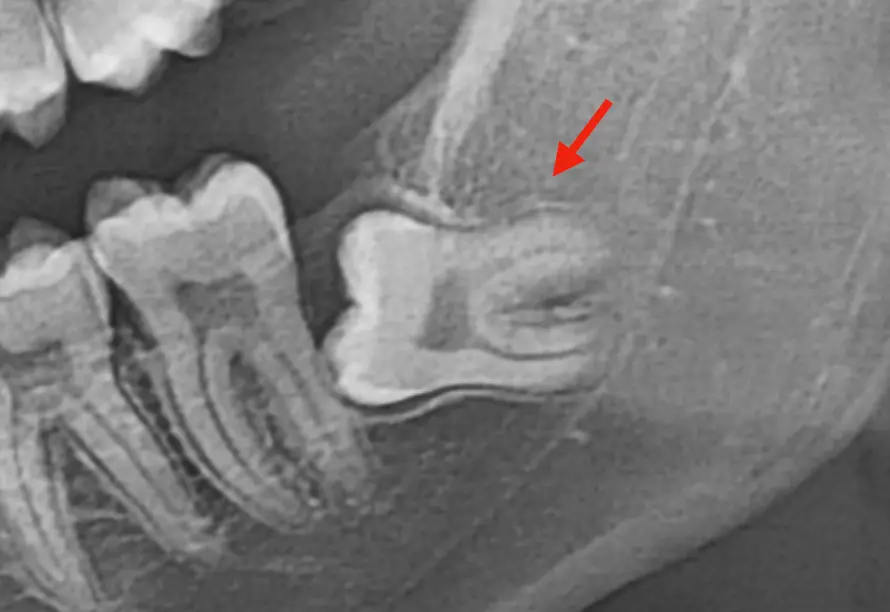

- 親知らずが横向きに埋まっている

- 骨の中に深く埋伏している

- 抜歯の際に骨を削る必要がある

特に、下あごの親知らずは骨が硬く、腫れやすい傾向があります。